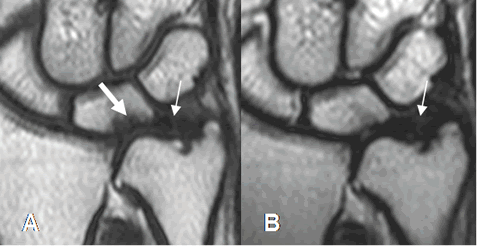

Fig 82. Degeneración del complejo del FCT.

A: RM coronal en T1 y B: RM coronal en T2. Lesión osteocondral del semilunar, por pinzamiento ulnar. (Flecha gruesa). Hay solución de continuidad del cartílago, en su tercio medio por ruptura. (Flecha delgada). Lesión tipo 2C.